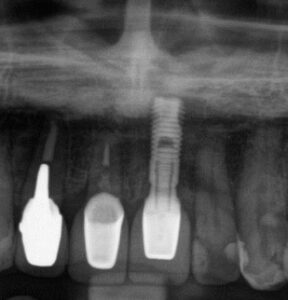

ここに示したのは白い歯が良いと判断された患者さんの例です。

The examples shown here are cases where patients opted for white teeth.